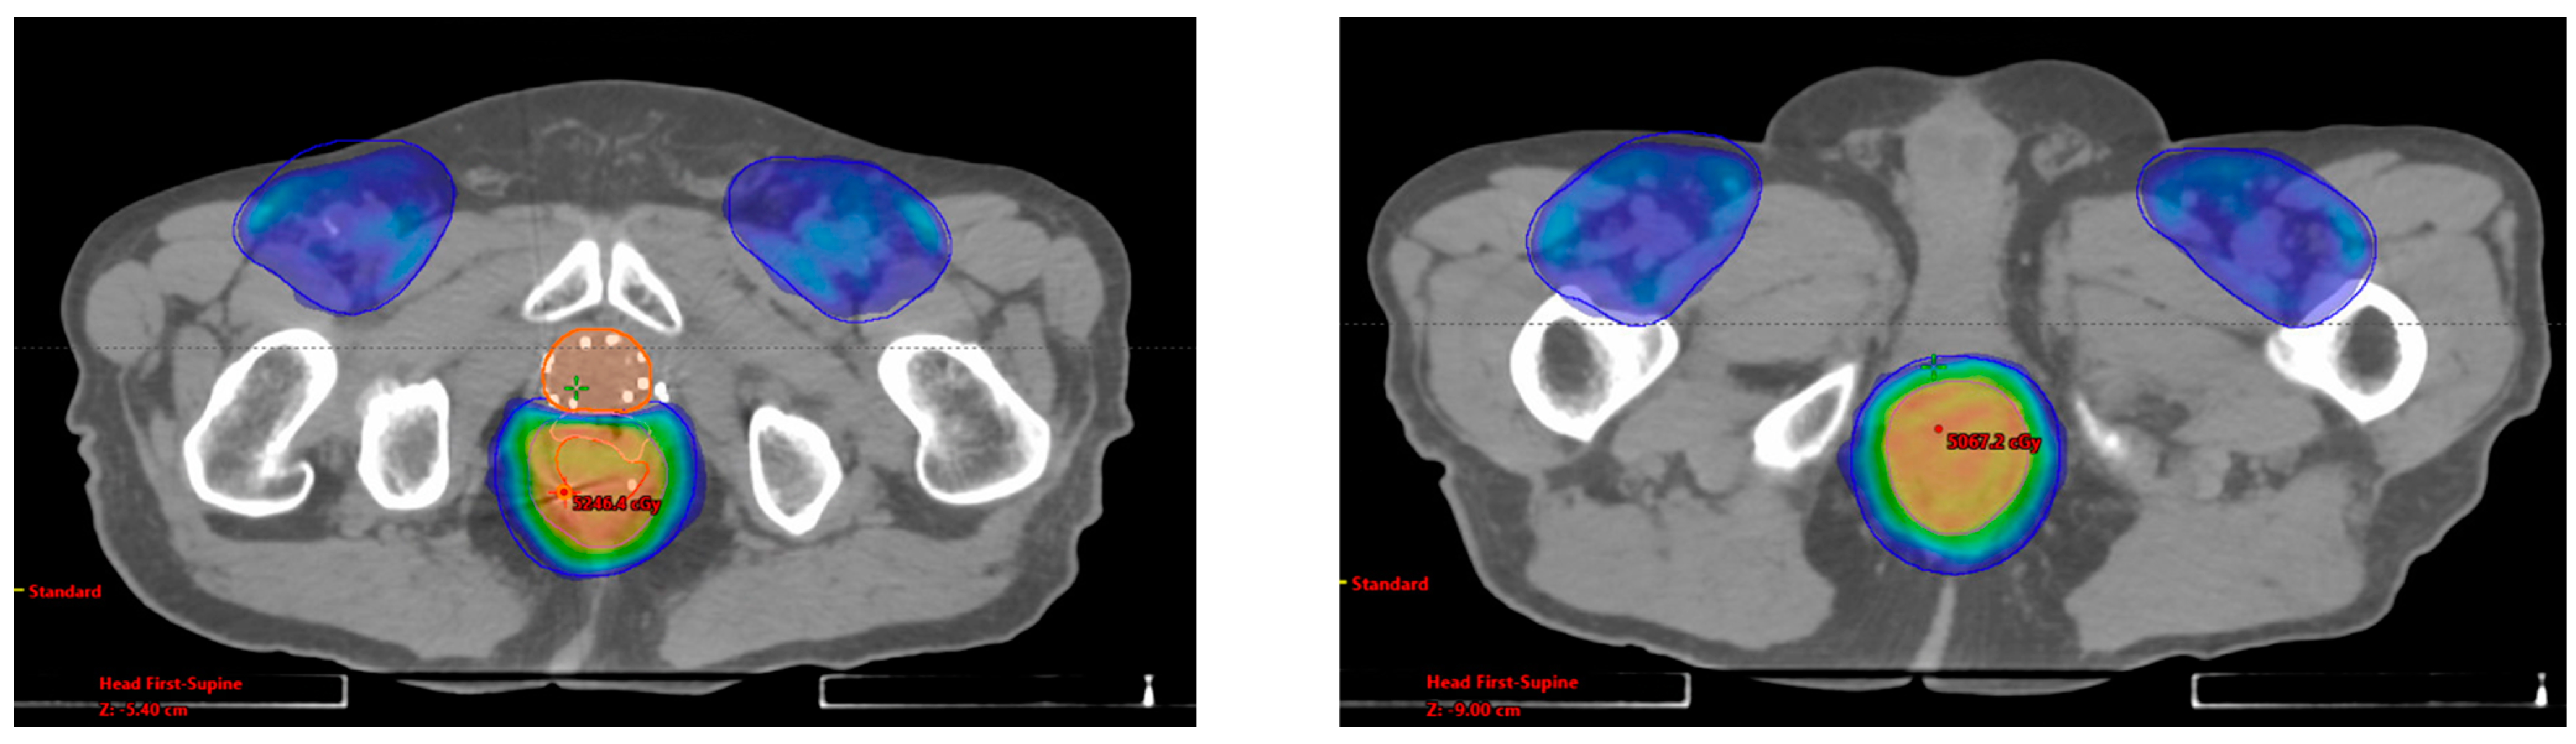

3.1. Case Report 1: Anal Squamous Cell Carcinoma

3.2. Case Report 2: Rectal Adenocarcinoma